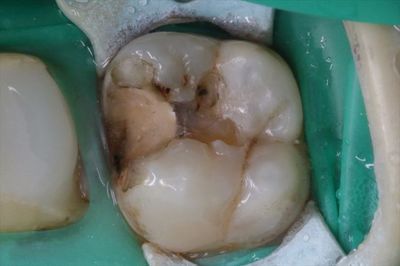

左上大臼歯の内部を染めたらこの状態でした。金属インレー 2019.01.26

過去の人工物を全て除去して、う蝕検知液で染色するとこの状態でした。